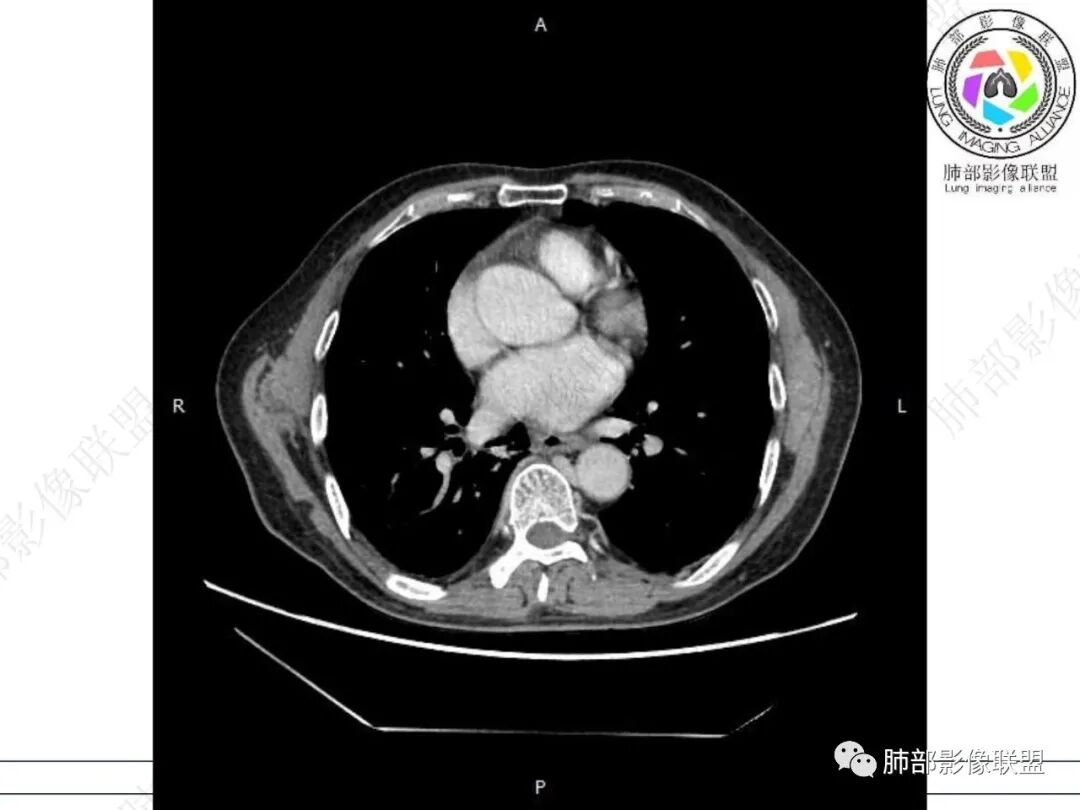

气管隆突下团片影,其内积气,与食道分界不清,食道壁增厚,管腔狭窄,右下肺实变影,支气管壁增厚,考虑食管支气管瘘并右下肺感染,食道肿瘤病变不除外

支持食管支气管瘘(考虑食管癌)伴后纵隔及右肺感染,食管管壁明显增厚,管腔狭窄,相邻右侧后纵隔内软组织内可见气体影,与食管分界不清,右肺有实变及不张。

右肺下叶背段条片状实变影,内可见支气管走行,支气管有狭窄有扩张,周围可见磨玻璃影,隆突下团片影,内密度不均可见气体影,与周围结构界限不清。食管下段壁增厚,管腔狭窄,右肺下叶慢性炎、肺不张,考虑食道肿瘤所致气管食管瘘。

老年男性,慢性病程,右肺下叶斑片影、斑点影、实变影,支气管轻度扩张,病灶整体稍收缩;食道壁增厚、肿胀、模糊,气管隆突及右后纵隔旁见软组织块影,其内见气泡影,均匀强化,符合食道支气管瘘伴周围炎症,右下肺炎症

男性69岁,咳嗽,咳痰10多年。两肺下叶有支气管扩张的改变,右肺下叶背段的片状实变阴影,有支气管的扭曲样穿行,有病灶的收缩,以及沿着支气管的 播散病灶,肺门纵隔内支气管隆突的上下呈大片状的实变影,结构比较混乱,食管显示的不清楚,伴有多发的淋巴结增大。临床上主要提及呼吸道的症状,但是没有提及消化道的症状。另外还见到肝内有多发的低密度病灶,考虑囊肿。

右肺下叶沿肺叶肺段分布斑片、条片状影,以下叶背段为显,边缘模糊,内可见支气管走行,局部支气管管壁增厚,右侧胸腔少量积液。纵隔隆突下可见不均匀软组织密度影,与周围结构分界不清,内见气体密度影,与食管及相邻右肺支气管之间未显示通道。邻近食管下段壁明显不规则增厚,增强后食管管壁明显不均匀强化,可见线样强化的连续完整粘膜影。

对比患者3月份的CT图,原隆突下存在增大钙化淋巴结,现在出现气体影,且钙化显示不清,应想到淋巴结结核破溃成瘘可能性。